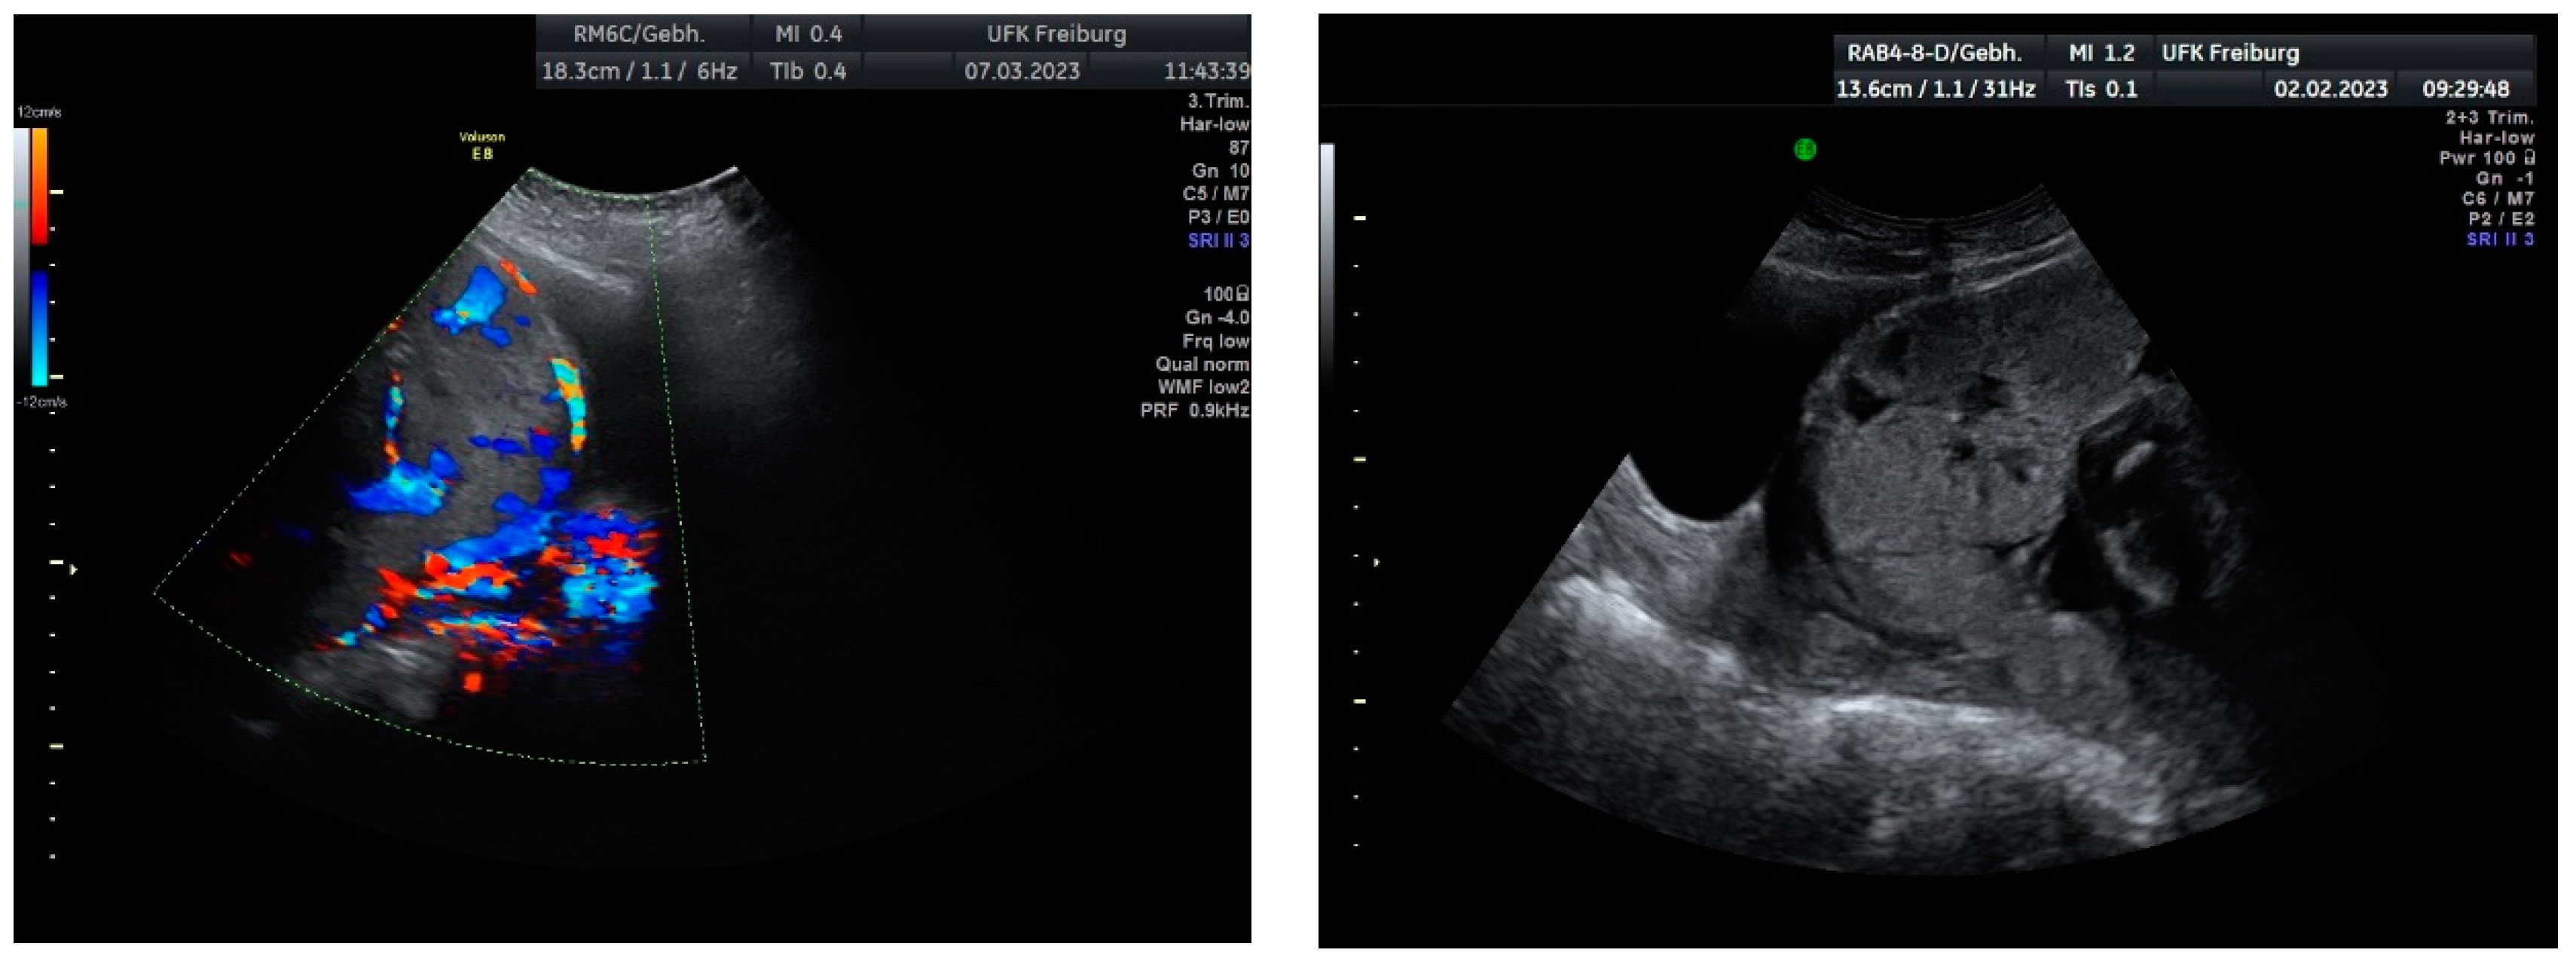

Sonographic findings (Figure 9):

Figure 9.

Irregular, large lacunae within the placenta, Hypervascularity, Turbulent flow inside the lacunae Diameter gaps.

Intraoperative findings (Figure 10):

Figure 10.

depict the uterus after hysterectomy with placenta previa and increta extending to the serosa. These images show the following findings:

- The uterus following a hysterectomy illustrates the presence of placenta previa with increta extending to the outermost layer of the uterine wall (serosa).

This confirms the suspected diagnosis of placenta previa with placenta increta, which necessitated the hysterectomy procedure to manage the condition.